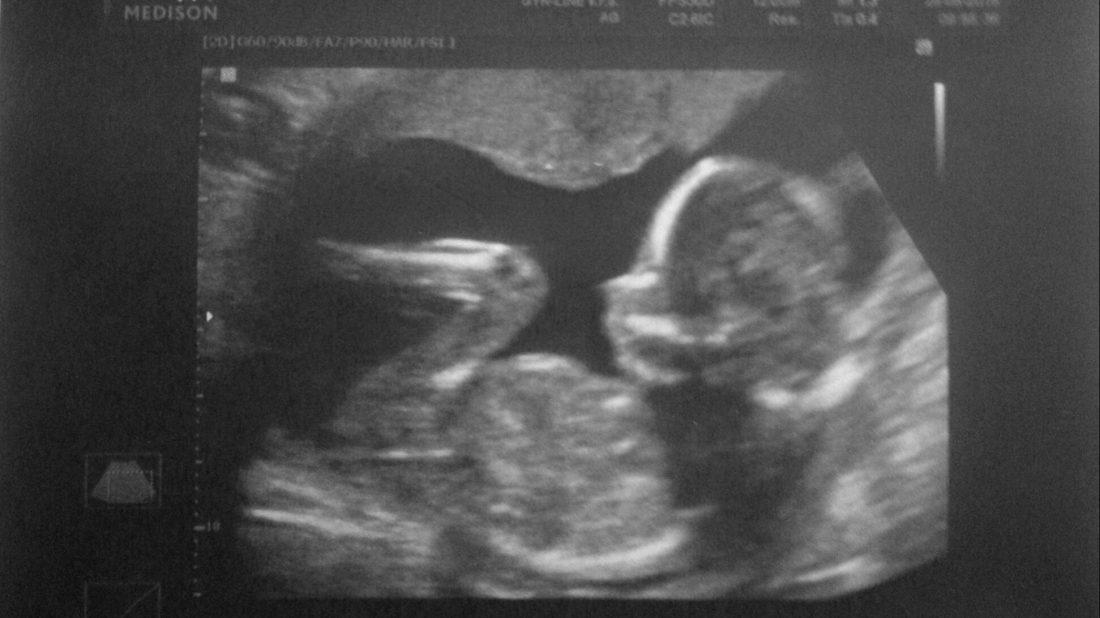

Vypadá úplně jinak než posledně. Je větší, zřetelnější, dokonce se stihnul i otočit. Hlavně je náš. Dnes se nám i ukázal. Trošku mu to trvalo, hned poskok, za chvíli měl kolínka způsobně u sebe. Ale dal si říct a bylo vidět, že mi v bříšku roste šikovný chlapeček. Přítel si sice tajně přál holčičku, která by byla jeho malá princeznička, v závěru mě ale ujistil, že je stejně moc rád za cokoli. Když si vzpomenu, co nám to způsobilo za trápení. Tehdy jsem poznala, že je to chlap mého života a budeme spolu v dobrém i zlém. Moje životní láska.

Vše ostatní bylo podle lékařky v pořádku, co se týká růstu i napohled. Ten kámen, který mi v tu chvíli spadnul ze srdce, museli slyšet hodně daleko. V naší době vůbec založit rodinu a donosit zdravé miminko, je velký problém a těm, co to člověk nejvíc přeje, osud mnohdy není nakloněn. Naděje umírá poslední, čehož jsme trošku i my důkazem. Přestali jsme nad tím přemýšlet a pak jsme sami byli překvapeni.

Radostnou zprávu, že to bude kluk, jsme museli zavolat celé rodině. Nejvíce netrpěliví byli budoucí prarodiče a tetičky, tzn. moje a přítelova sestra. Poprosila jsem lékařku, zda by mi zároveň vystavila žádanku na ultrazvuk srdíčka, abychom měli jistotu, že i v této oblasti je náš chlapeček v pořádku.